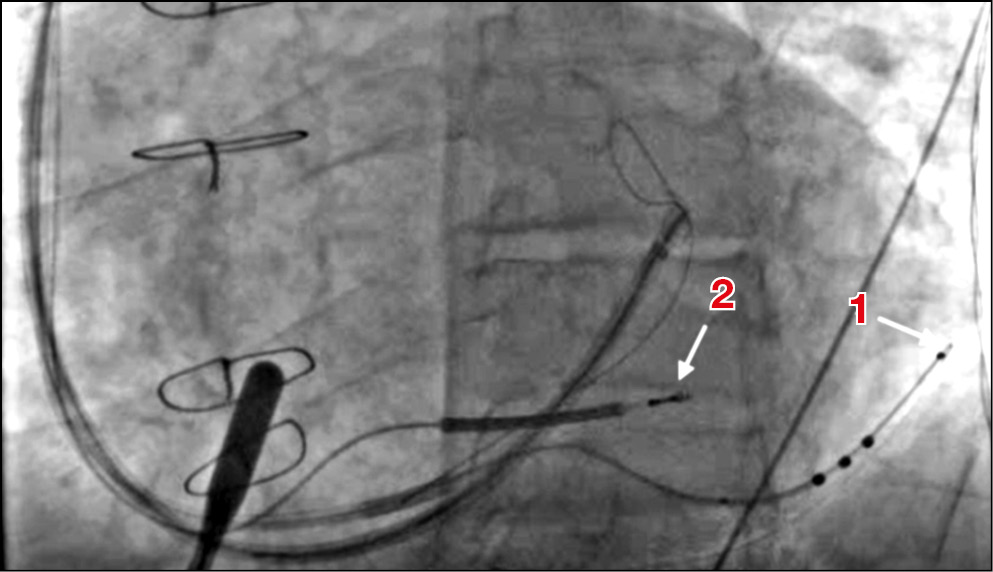

Было принято решение использовать ортодромный ловушечный метод позиционирования левожелудочкового электрода с целью преодоления имеющихся анатомических трудностей. В большую вену сердца была введена вторая система доставки, по которой проведена ловушка типа Goose Neck (гусиная шея) для захвата дистального конца коронарного проводника в большой вене сердца с целью формирования замкнутой петли (рис. 3, а). После создания петли из коронарного проводника электрод удалось завести и позиционировать в нужную зону (рис. 3, б), при этом стимуляционный полюс был расположен вблизи целевой зоны, что видно на правой и левой косой проекциях при рентгеноскопии (рис. 3, б; 4). Параметры порога стимуляции с дистального полюса левожелудочкового электрода в данной области — 2,0 В при 0,4 мс, сенсинг (порог чувствительности) — 11 мВ, импеданс — 750 Ом. Параметры порога стимуляции с полюса ring 2 (второй кольцевой полюс) левожелудочкового электрода (расценен как наиболее предпочтительный для стимуляции по причине более близкого расположения к целевой зоне стимуляции левого желудочка) — 1,8 В при 0,4 мс, порог чувствительности — 7 мВ, импеданс — 698 Ом.

Рис. 4. Позиционированные правожелудочковый и левожелудочковый электроды в левой косой (30°) проекции: 1 — дистальный конец левожелудочкового электрода, располагающийся практически в средней трети латеральной стенки левого желудочка; 2 — дистальный конец правожелудочкового электрода, установленного в верхушку сердца (верхушечная часть межжелудочковой перегородки). / Fig. 4. The right ventricular lead and the left ventricular lead it the end of the operation (left anterior oblique, 30°): 1 — the distal tip of the left ventricular lead is in the middle part of the lateral ventricle wall; 2 — the distal tip of the right ventricular lead is in the heart apex.